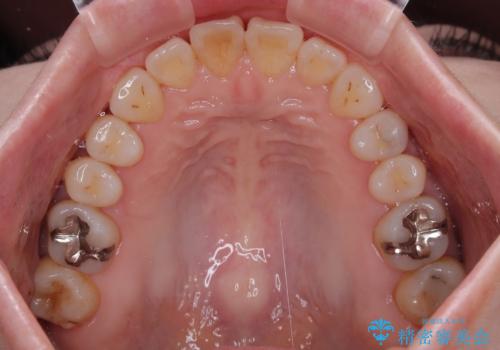

前歯のデコボコをインビザライン・モデレートで矯正治療

- 上下前歯のデコボコを気にして来院された患者様です。

安価なインビザラインパッケージを用いての治療を希望されており、デコボコの程度が中等度であったため、インビザライン・モデレートを用いて矯正治療を行うこととしました。

インビザライン・モデレートは、製作できるアライナーの枚数に制限があるため、移動可能な量に限りがあるものの、インビザライン・ライトよりも枚数が多いため、幅広い症例に対応可能です。